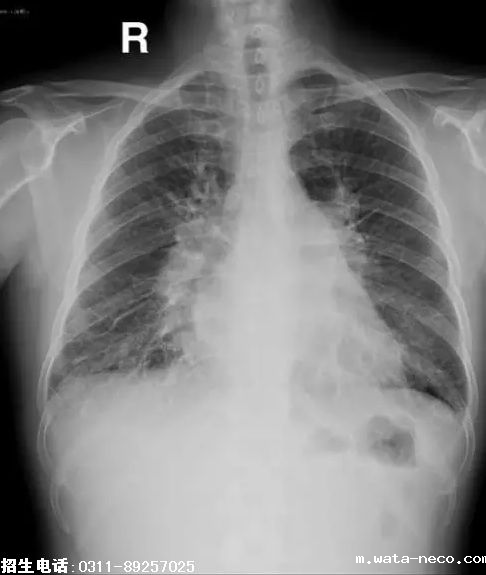

1、题干:男,55岁。腹痛,呕血1次。结合X线片,此诊断为

A、胸腔积液

B、二尖瓣型心

C、主动脉型心

D、普大型心

E、肺炎

答案:B

解析:心脏投影呈现梨形,主要是心腰部分向外膨大的一种体现如下图。由于心脏的心腰部份是肺动脉和左心房共同构成。所以任何引起肺动脉膨大(见于肺动脉高压)和左心房扩大(见于二尖瓣狭窄)的疾病都会出现梨形心。尤其是二尖瓣狭窄时更为典型,因为二尖瓣狭窄时除左心房淤血增大外,长时间的肺部淤血还会出现肺动脉高压。这样左房增大和肺动脉高压同时出现使得心腰向外膨出。另外二尖瓣狭窄,流入左心室的血液减少,左心室会较正常减小就使心腰部分的膨大显得更加明显。所以梨形心最常见于二尖瓣狭窄所以又叫作二尖瓣形心。